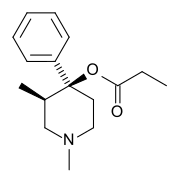

4-Phenylpiperidines

Prodines

- Allylprodine

- (α/β)-Meprodine

- Desmethylprodine (MPPP)

- PEPAP

- (α/β)-Prodine

- Prosidol

- Trimeperidine (promedol)

Structures